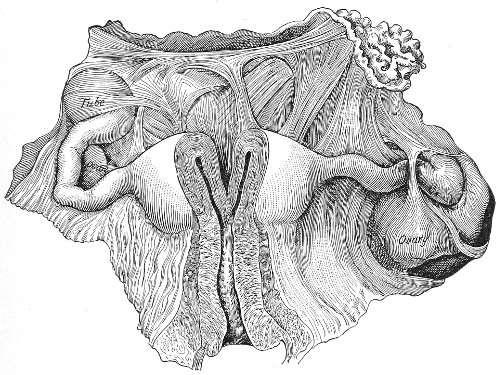

Vaginal and Bimanual Examination.—Having examined and noted the condition of the external genitals, the physician should next proceed to examine the vagina. The index finger of the right or the left hand should be gently introduced into the vagina. The condition of the vaginal walls, and the direction, consistency, form, etc. of the vaginal cervix, may be determined. The shape and size of the os uteri should be noted. The ulnar edge and the tips of the fingers of the other hand should then be placed upon the abdomen, immediately above the symphysis pubis, and gently pressed backward and downward toward the vaginal finger 24 (Fig. 2). In this way the various pelvic organs, the uterus, Fallopian tubes, ovaries, and ureters, may be palpated between the two hands, and their position, size, shape, and consistency may be determined. Such an examination is, of course, made much more easily in a thin woman than in a fat one. A thin woman a few weeks after labor may be examined most easily, on account of the relaxation of the abdominal and vaginal walls.

Fig. 2.—Bimanual examination.

In making the bimanual examination the structures 25 should be palpated methodically in order. The vaginal finger notes the condition of the cervix uteri. If the fundus be in the normal position, the uterus can then be taken between the abdominal hand (upon the fundus) and the vaginal finger (upon the cervix) (Fig. 3). The shape, size, mobility, and consistency are noted. The vaginal finger is then passed anteriorly and laterally toward either uterine cornu, while the abdominal fingers pass over to the posterior aspect of the same cornu. The ovarian ligament and the proximal end of the Fallopian tube may thus be felt. Passing farther outward, the whole of the tube and the ovary may be examined. The same procedure is then applied to the opposite side.

Fig. 3.—Bimanual examination; median sagittal section of the pelvis.